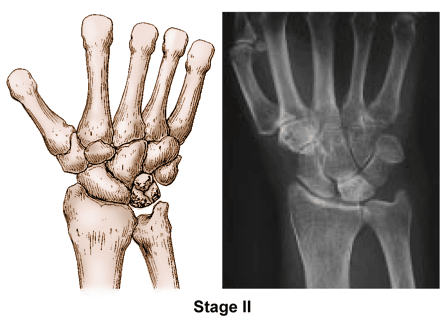

Stage II

• The lunate bone begins to harden due to the lack of blood supply during Stage II. This hardening process is called sclerosis and is an abnormal increase in bone density.

• The lunate will appear brighter or whiter in areas on X-rays, which indicates that the bone is more dense.

• To better assess the condition of the lunate, your doctor may order either an MRI scan or a computed tomography (CT) scan.

• The most common symptoms during this stage include wrist swelling and intermittent pain, particularly when force is applied to the wrist, such as with weightbearing.

Kienböck's disease stage 2

Stage II. (Left) This illustration shows that the lunate has hardened with more than one fracture line. (Right) The lunate is brighter than the surrounding bones, which indicates that the bone is more dense.